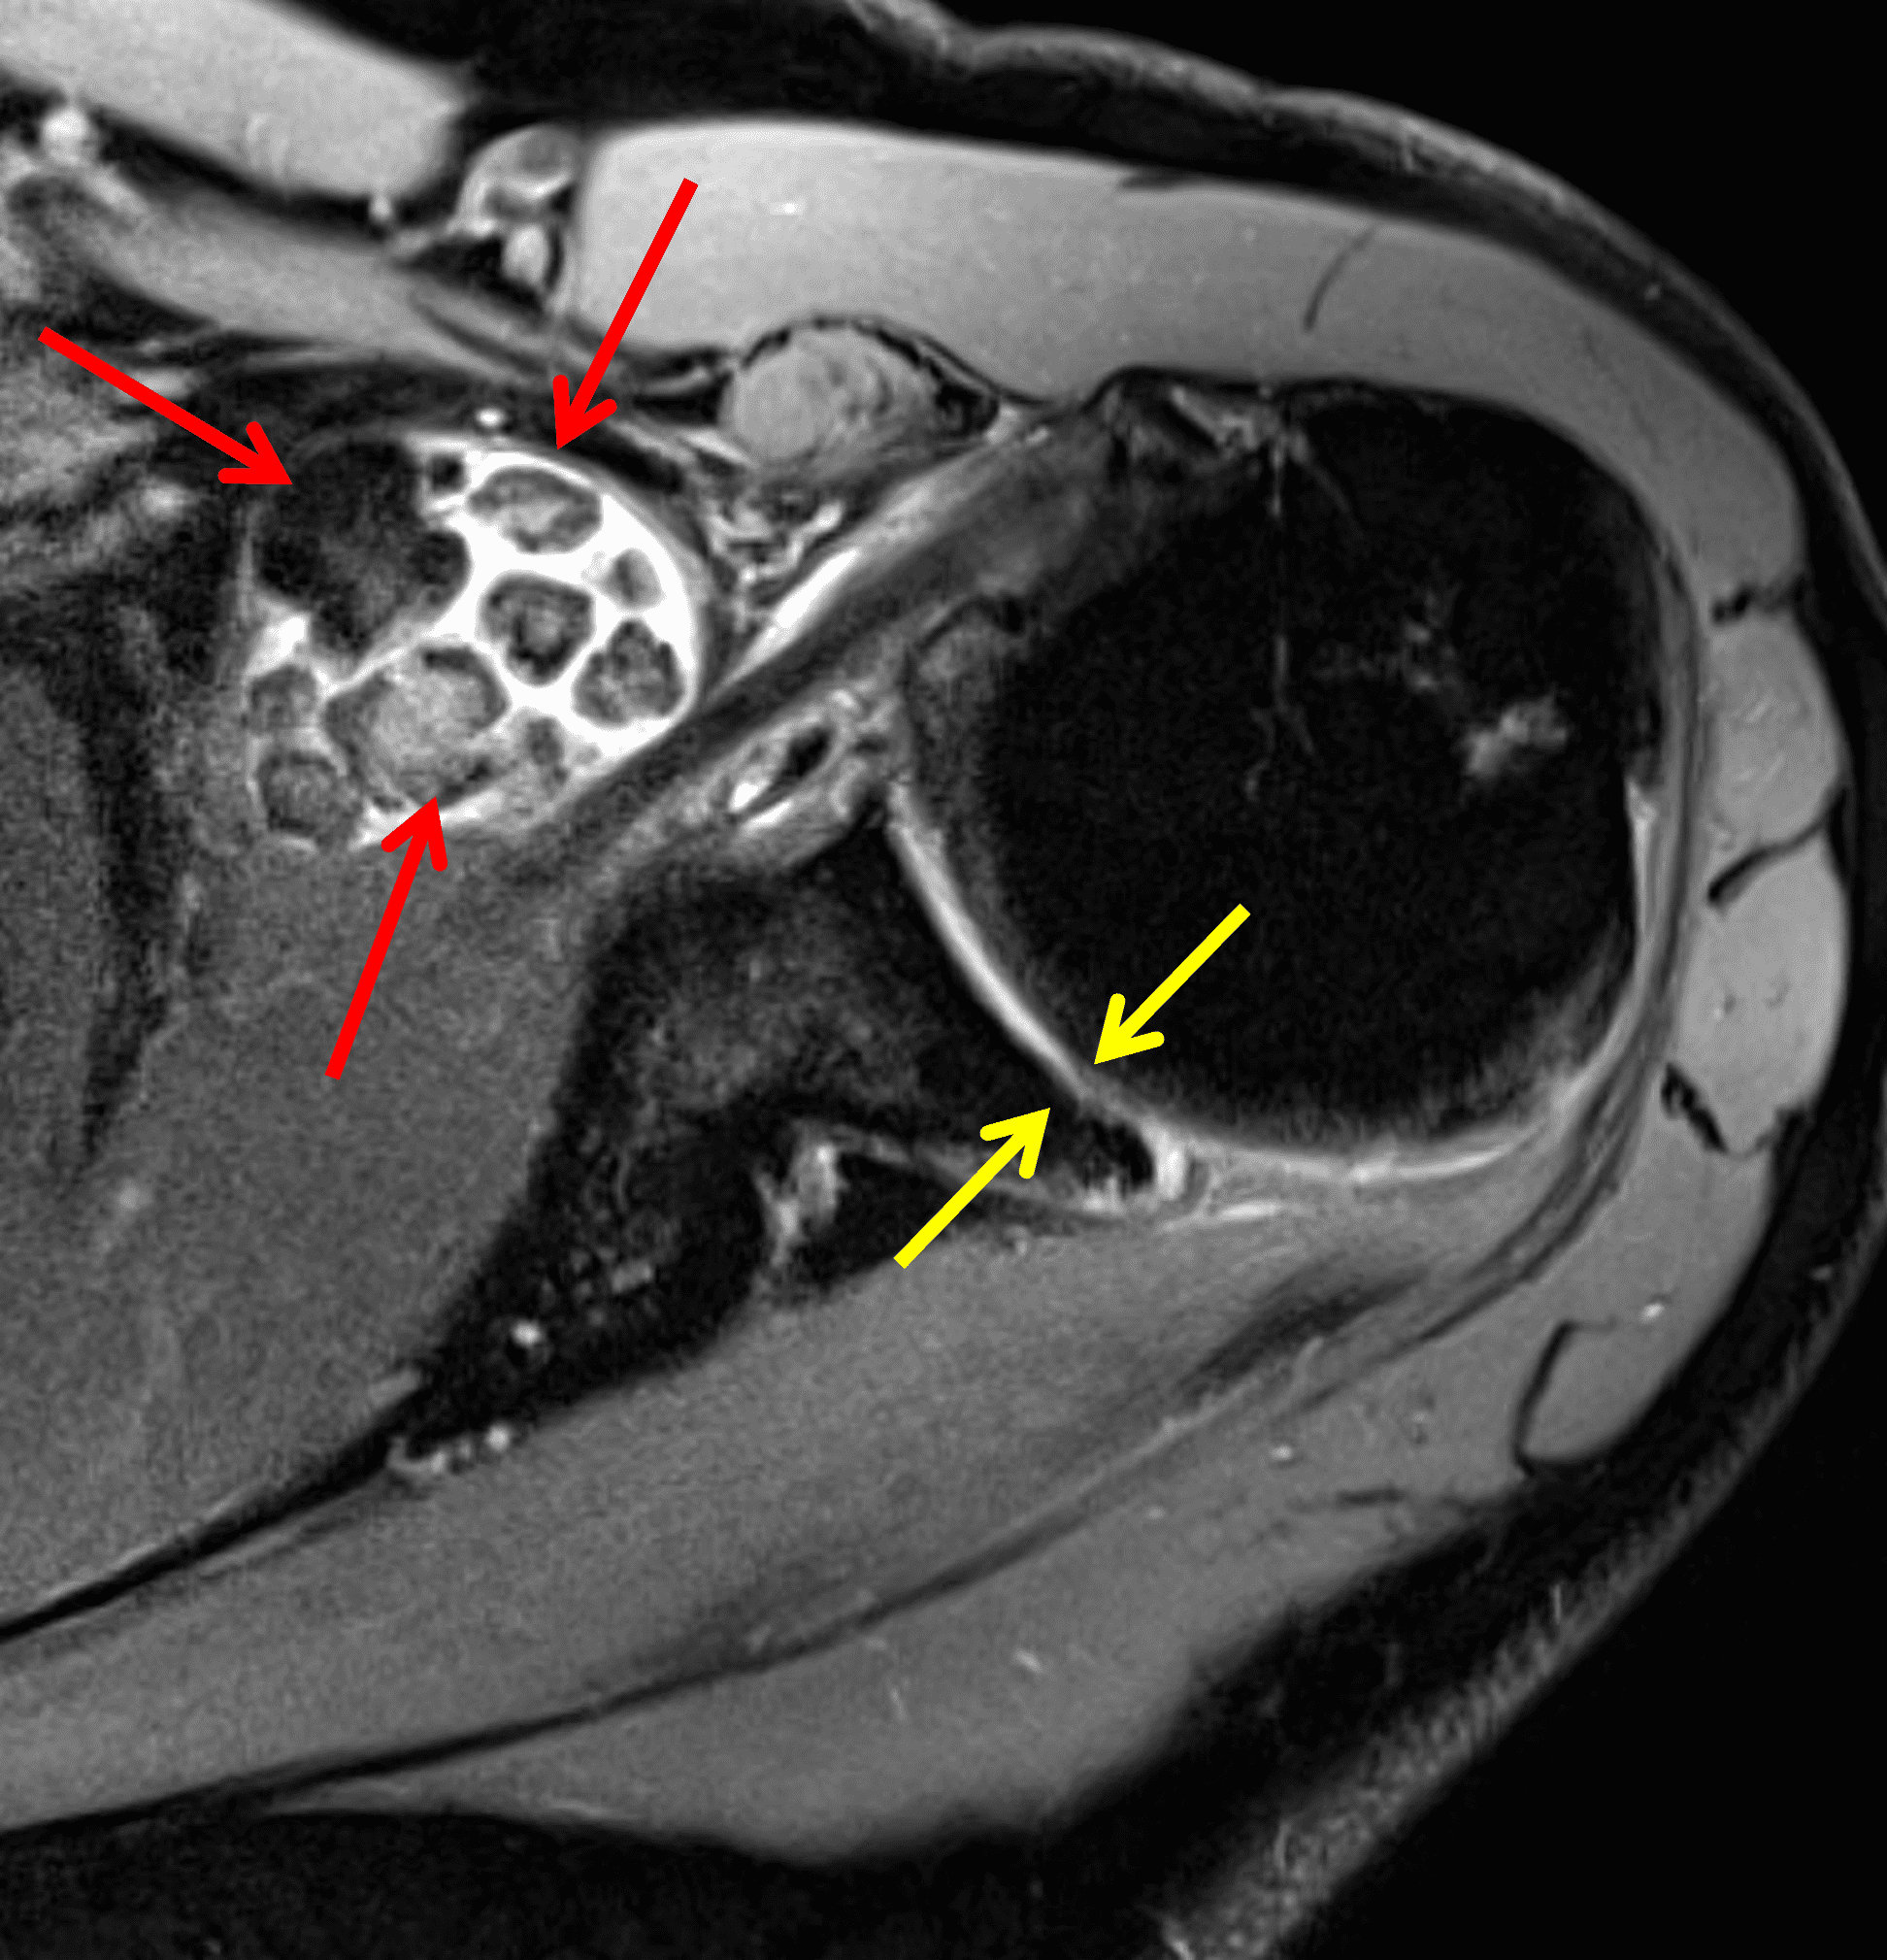

Figure 4: Secondary osteochondromatosis (loose bodies) in the shoulder joint. An axial fat-suppressed T2-weighted image shows multiple intra-articular bodies of variable size (red arrows) and severe glenohumeral cartilage (yellow arrows) due to osteoarthrosis.